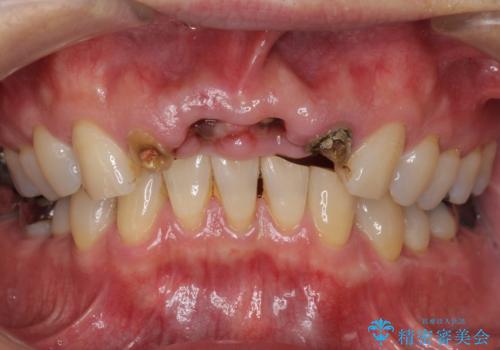

- お風呂場で転んで上の前歯が2本抜けてしまったことを主訴に来院された患者様です。

精査したところ、左上の側切歯(左上2)も破折しており保存不可能な状態でした。

左上の側切歯(左上2)を抜去し、右上の側切歯(右上2)の再根管治療後、セラミックのブリッジによる補綴を行いました。